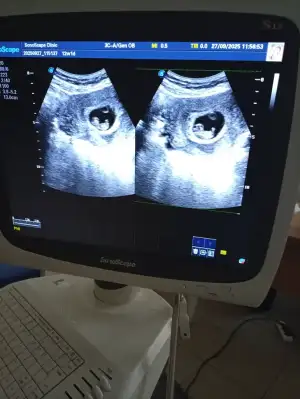

Vajinal görüntü, beni de yorumlar mısınız lütfenAbdominal görüntüyse erkek olabilir

Merhaba scula gire erkeke gibi duruyor ama.daha cok kucuk Rabbim.gonlunuze gire versin insallah saglkli sihatli10 haftalık ama tahmin yürütebilecek biri var mı :)

Scula gore erkek gibi gordum ama nubu daha gozukmemis cikinti goremedjm Rabbim gonlumize gore hayirlisini versin insallahMerhabalar rica etsem banada yorum yaparmısınîz 12 haftalık

Merhaba banada bakarmisiniz?Görüntü çok net değil ama erkek olabilir